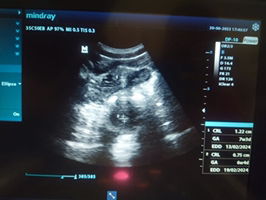

Mau tanya, kalo hamil 5 minggu kantung janin belum terlihat, apakah normal?

Dalam hamil 5 minggu, belum terlihatnya kantung janin bisa jadi hal yang normal. Setiap kehamilan itu unik dan ada banyak faktor yang mempengaruhi perkembangan awal. Kadang-kadang, waktu ovulasi bisa sedikit berbeda dari yang diperkirakan, sehingga usia kehamilan bisa lebih muda dari yang kita kira. Sebaiknya, konsultasikan dengan dokter untuk mendapatkan penjelasan lebih lanjut dan memastikan semuanya baik-baik saja. Mereka bisa melakukan pemeriksaan lebih lanjut, seperti USG, untuk melihat apa yang terjadi. Yang terpenting, jaga kesehatan dengan mengonsumsi makanan bergizi dan suplemen yang tepat selama hamil. Jika butuh suplemen, bisa cek di sini: https://shope.ee/5fSnMnSlux. Semoga semua berjalan lancar! https://shope.ee/9KMNPOoFkR

Baca laginormal apalagi kl haidnya gak teratur, biasanya usia kehamilannya lebih kecil dari hphtnya

normal banget malah ada yg dibilang masih penebalan dinding rahim dtg lg lg pas 8week

masih normal Bun coba nunggu 8-9 w biasanya udah keliatan

Normal. Usg ulang 2 minggu lagi bu